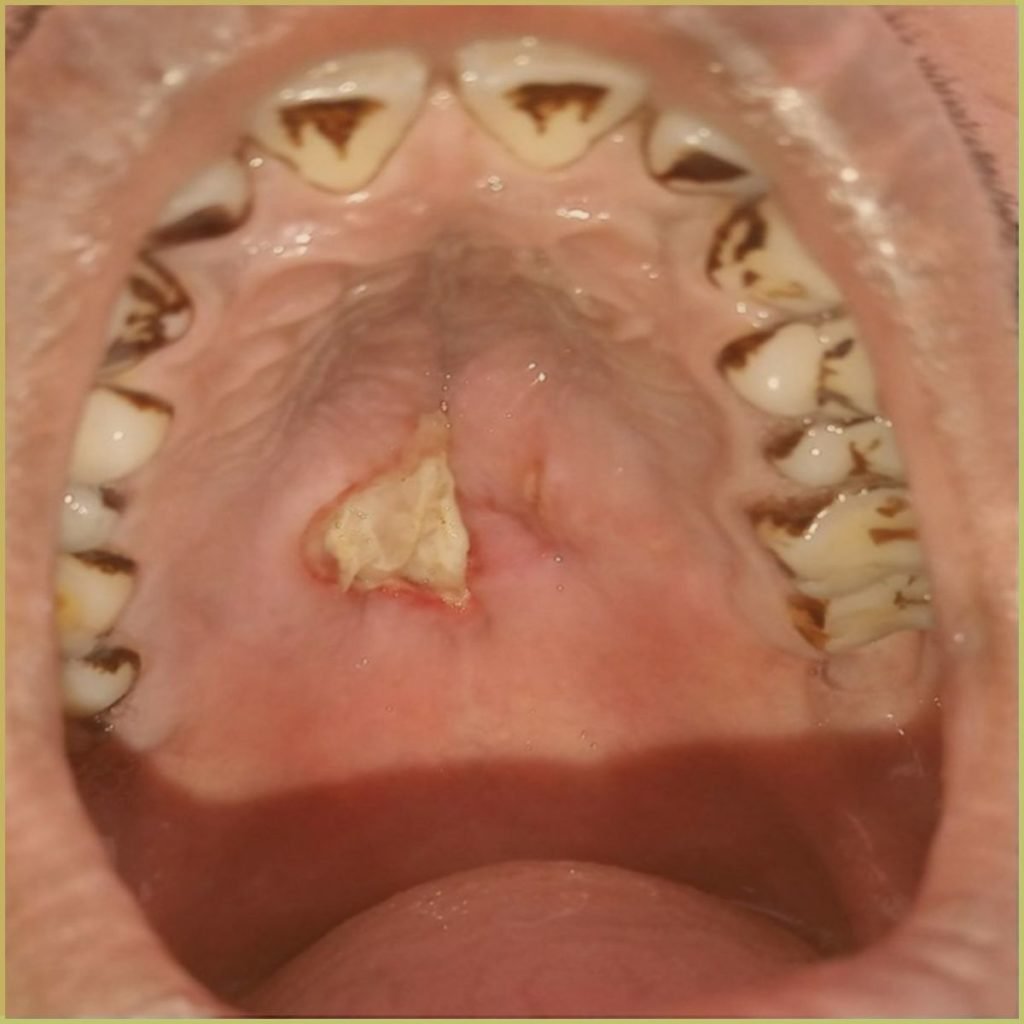

NECROTIZING SIALOMETAPLASIA

Necrotizing Sialometaplasia is a benign, self-limiting inflammatory salivary gland lesion which may clinically and histologically mimic squamous cell carcinoma or mucoepidermoid carcinoma. Trauma to a minor salivary gland leads to local ischemic injury of the salivary gland lobules, resulting in the worrisome clinical appearance. The common clinical presentation includes:

- Most commonly affects major and minor salivary glands of the palate.

- Unilateral dysesthetic to painful submucosal swelling that turns into a necrotic crater/ulcer.

- May extend to and involve deep soft tissues and palatal bone.